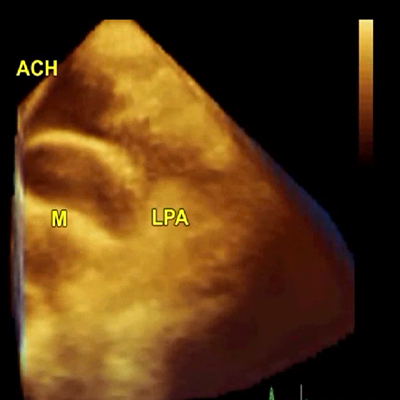

3D TEE: narrow mitral orifice

3D TEE: narrow mitral orifice

3D TEE: narrow mitral orifice

3D TEE: narrow mitral orifice